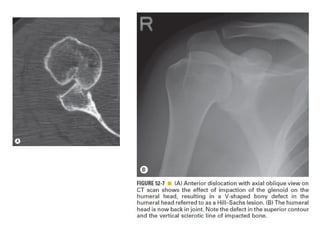

Skeletal trauma was presented by Dr Laith Fadhel with reference to Grainger's Diagnostic Radiology textbook. The presentation covered skeletal trauma as assessed through diagnostic radiology techniques. Key findings and treatments for skeletal injuries were likely discussed.